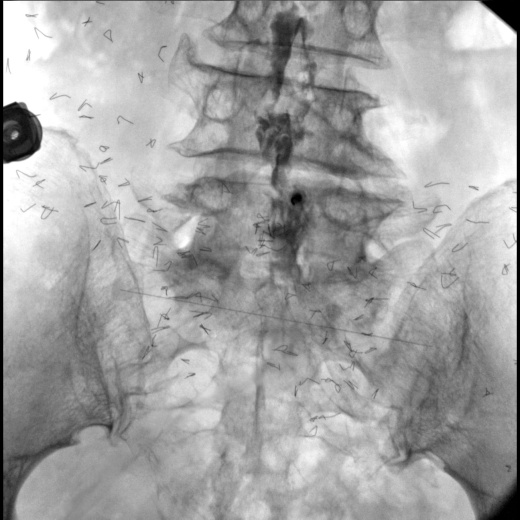

В качестве приемника используется динамический плоскопанельный детектор 26×26 см с разрешающей способностью более 4,5 пар.лин./мм., позволяющий визуализировать мельчайшие объекты с высоким разрешением. За счет применения динамического плоскопанельного детектора отсутствует эффект дисторсии, что повышает диагностическую значимость исследований. Большой диапазон выбора значений кадров с секунду при импульсной рентгеноскопии позволяет значительно снизить лучшею нагрузку, при этом при необходимости возможно проводить исследования с частотой до 30 кадров в секунду.

- Мобильный цифровой рентгенохирургический аппарат на базе штатива типа С-Дуга с цифровым плоско панельным детектором 26х26 см;